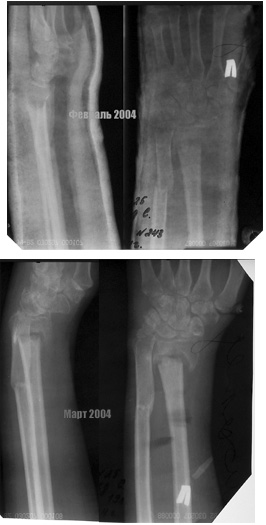

Травма в конце ноября 2003. Лечение - гипсовая лонгета по настоящее время. На контрольных рентгенограммах видно отсутствие консолидации, рассасывание в области перелома лучевой кости, остеопоротические изменения костей. Есть также гипэстезия 4,5 пальцев кисти, выраженная атрофия мышц. Функция кисти=0.Думали, что можно сделать: однозначно нужно выполнять освежение отломков, костную пластику, остеосинтез. Причем не медлить! Вопрос в том, как зафиксировать, все упирается в опасения прорезывания любых фиксаторов. Кроме того - что делать с локтевой костью - она работает как распорка. Резецировать ли ее головку, или имеет смысл сегментарно резецировать диафиз с последующим остеосинтезом?Просьба поделиться своими соображениями.

Не совсем согласен с вашим решением * не медлить* с фиксацией перелома лучевой кисти при отсутствии функции кисти. После столь продолжительной и,

как видно по рентгенограммам, бесполезной иммобилизации и мышечная атрофия, и порозность фрагментов очевидно являются следствием отсутствия функции. На данном этапе я бы скорее отправил больного к физиотерапевту на разработку движений пястно-фаланговых и межфаланговых суставов, если недеель через 6 тугоподвижность суставов начнет разрешаться и появится надежда на восстановление функции кисти, тогда и можно рассматривать различные подходы (удлинение луча или костная пластика с фиксацией Т-образной пластиной или укорачивающая остеотомия локтевой кости и т.д). Если после курса физио никаких намеков на функциональность кисти не появится при сохранении жалоб на боли вокруг лучезапястного сустава, то, пожалуй, можно будет ограничиться артродезом с одновременной пластикой несращения (так или иначе, пластина укладывается по тыльной поверхности, так, что обнажить зону нестращения и восстановить длину луча не должно быть большой проблемой)